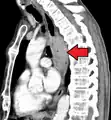

Additional testing is needed to assess how much the cancer has spread (see #Staging, below). Computed tomography (CT) of the chest, abdomen and pelvis can evaluate whether the cancer has spread to adjacent tissues or distant organs (especially liver and lymph nodes). The sensitivity of a CT scan is limited by its ability to detect masses (e.g. enlarged lymph nodes or involved organs) generally larger than 1 cm.[41][42] Positron emission tomography is also used to estimate the extent of the disease and is regarded as more precise than CT alone.[43] Esophageal endoscopic ultrasound can provide staging information regarding the level of tumor invasion, and possible spread to regional lymph nodes.

Contrast CT scan showing an esophageal tumor (axial view)